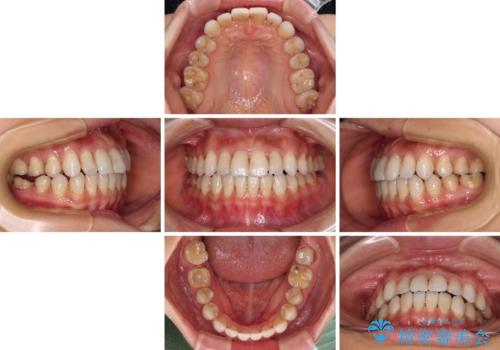

【モニター】開咬を治したい インビザラインによる矯正治療

- 上下前歯の開咬とデコボコを気にして来院された患者様です。

開咬(オープンバイト)はインビザラインによる矯正治療がワイヤー装置と比べて圧倒的に有利であるため、インビザラインによる矯正治療を行うこととしました。

通院されなかった時期があって治療期間が長くなったり、奥歯に抜歯が必要な歯があったりと、治療は一筋縄にはいきませんでしたが、何とか治療を終えることができました。

今後はインプラント治療やむし歯治療を進めて行く予定です。